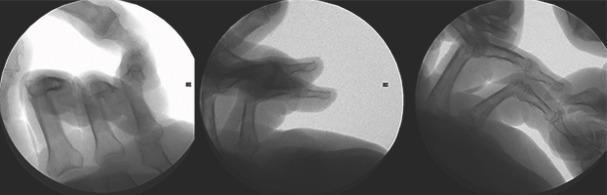

The patient is an 80-year-old right-hand dominant retired male with bilateral hand contractures and palmar fibromatosis. His medical history is notable for Type II diabetes mellitus and metastatic thyroid cancer. The patient underwent Xiaflex injection of the left small finger and returned 4 days later for planned release. An appreciable release of the contracture was noted; however, there was a concern for plastic deformation of the proximal phalanx as a result of the manipulation. X-rays confirmed the fracture and apex volar angulation at the base of the proximal phalanx. The fracture appeared amenable to non-operative treatment. The patient has been followed closely and has had no pain or tenderness at the fracture site and minimal swelling. X-rays at 1 week and 1 month showed maintained alignment and signs of consolidation at the fracture site. The patient is currently 4-month post-fracture, and no further intervention has been pursued.